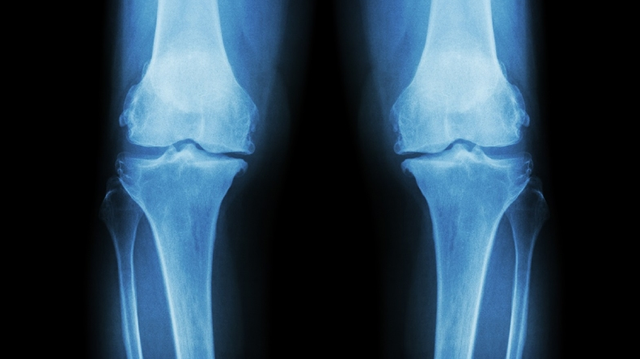

Sụn xương là một loại mô liên kết mềm dẻo tham gia vào cấu trúc của bộ xương và được tìm thấy ở nhiều nơi trong cơ thể người. Sụn xương đóng vai trò như một lớp đệm trong các khớp, nó hoạt động tương tự như một bộ phận giảm xóc, bảo vệ và giúp giảm chấn động, ngăn chặn sự cọ xát giữa hai đầu xương khi di chuyển. Cùng tìm hiểu cụ thể hơn sụn xương có tác dụng gì qua nội dung sau đây.